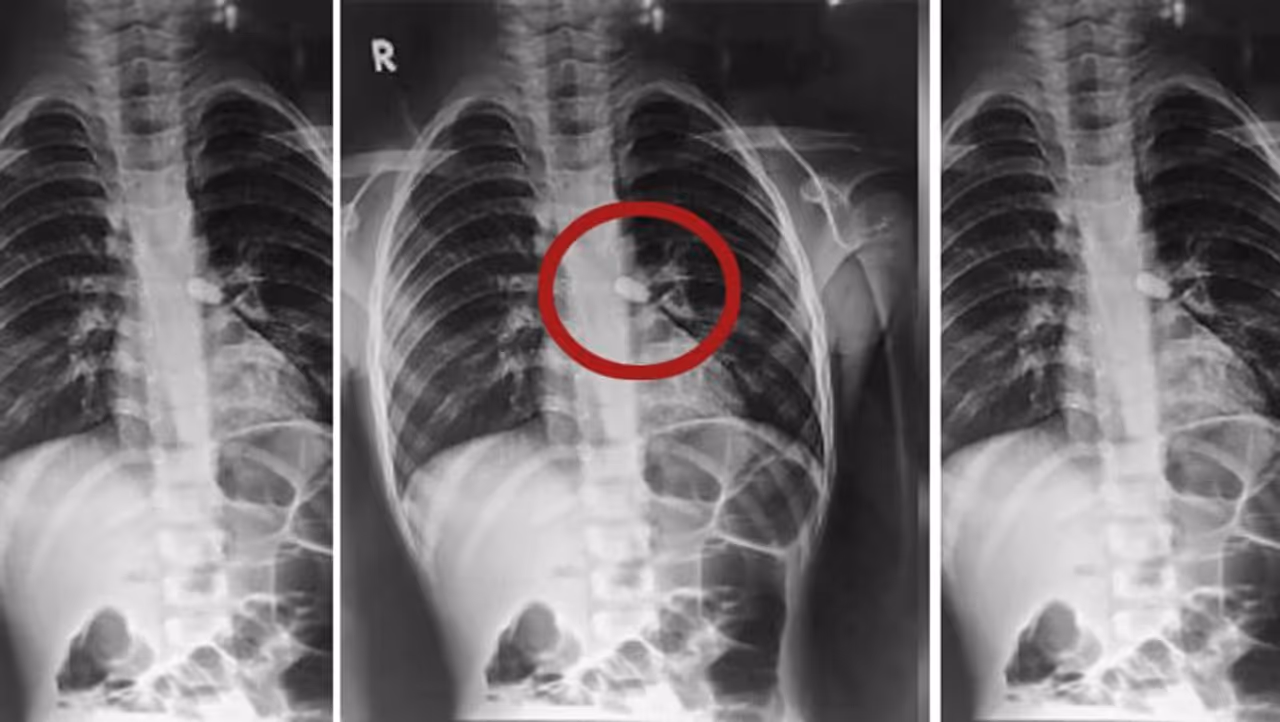

इस बच्ची का ऑपरेशन बीकानेर के ईएनटी हॉस्पिटल में किया गया। बच्ची को उसके परिजन गले में दिक्कत और श्वांस लेने में तकलीफ के बाद पीबीएम पीडिएट्रिक हॉस्पिटल लाए थे। चेकअप के बाद डॉक्टर समझ गए कि बच्ची ने कुछ निगला है। उसे वहां से ईएनटी हॉस्पिटल भेज दिया गया। यहां के डॉक्टरों की मानें, तो वे सालभर में ऐसे 200 बच्चों को इलाज करते हैं, जो कुछ निगल लेते हैं। डॉक्टर एंडोस्कोप के जरिये 10-20 मिनट में चीज निकाल देते हैं। लेकिन इस बच्ची के मामले में ऐसा नहीं था। दरअसल, बच्ची ने चिकना पत्थर निगला था। उसे डॉक्टर निकालने को होते, तो वो विंड पाइप तक आकर फिर से छूट जाता।

बच्ची की जान बचाने डॉक्टरों ने ईएनटी-एनस्थीसिया के 10 डॉक्टरों, नर्सों और ओटी स्टाफ के साथ दो स्पेशलिस्ट डॉक्टरों की एक टीम बनाई। ये स्पेशलिस्ट थे ईएनटी के प्रोफेसर-एचओडी डॉ. दीपचंद और डॉ. गौरव गुप्ता। इसके बाद बच्ची के गले में छेद करके पत्थर निकाला गया। बच्ची को दो दिन बाद हॉस्पिटल से छुट्टी दे दी गई। डॉक्टरों ने बताया कि इस तरह के कई सालों में आते हैं।